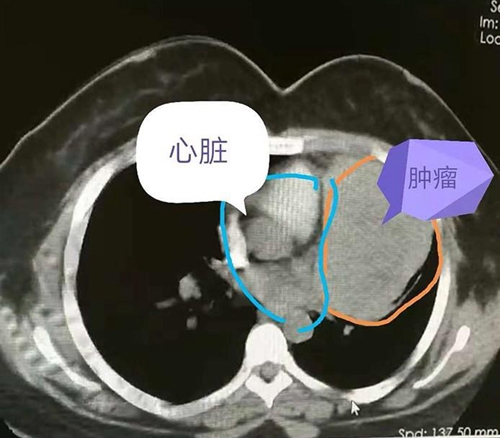

可是,女孩没有想到的是,肿瘤的生长超出预期,最近两周突然出现睁不开眼的情况。再次就医,医生告诉她,这应该是胸腺瘤生长造成的重症肌无力。再次检查,发现肿瘤较8月份明显长大, 同时发现肿瘤压迫了心脏大血管和肺组织。

手术中发现肿瘤侵犯了肺动脉外膜,对肺也有侵犯,经过2个多小时的仔细剥离,终于完整切除了肿瘤,同时,还切除了部分心包和受侵犯的肺组织。